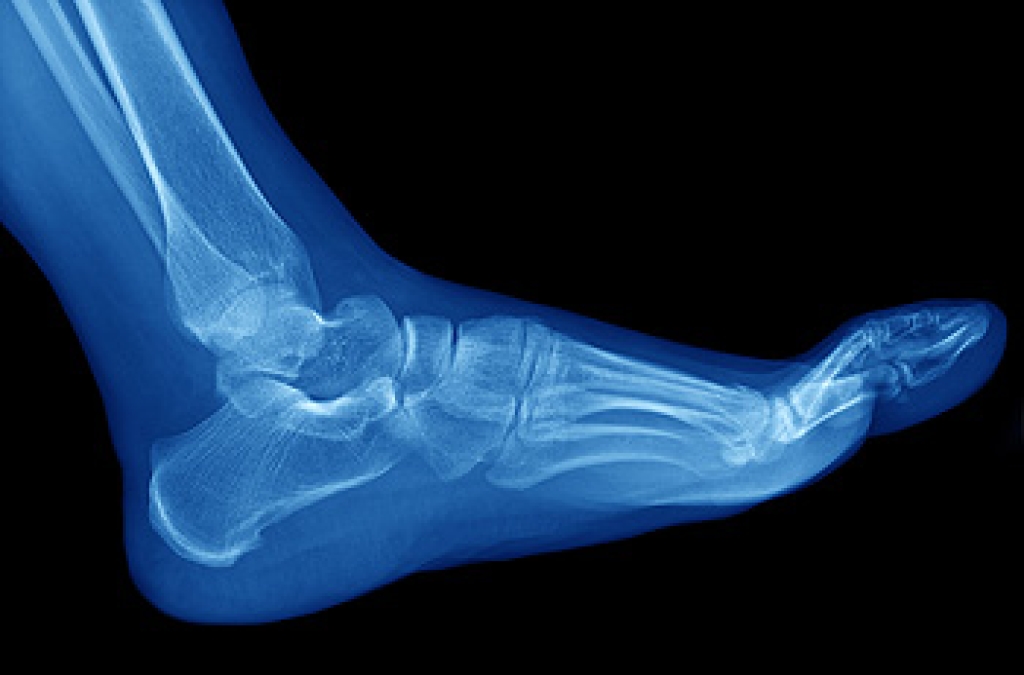

A broken ankle is experienced when a person fractures their tibia or fibula in the lower leg and ankle area. Both of these bones are attached at the bottom of the leg and combine to form what we know to be our ankle.

When a physician is referring to a break of the ankle, he or she is usually referring to a break in the area where the tibia and fibula are joined to create our ankle joint. Ankles are more prone to fractures because the ankle is an area that suffers a lot of pressure and stress. There are some obvious signs when a person experiences a fractured ankle, and the following symptoms may be present.